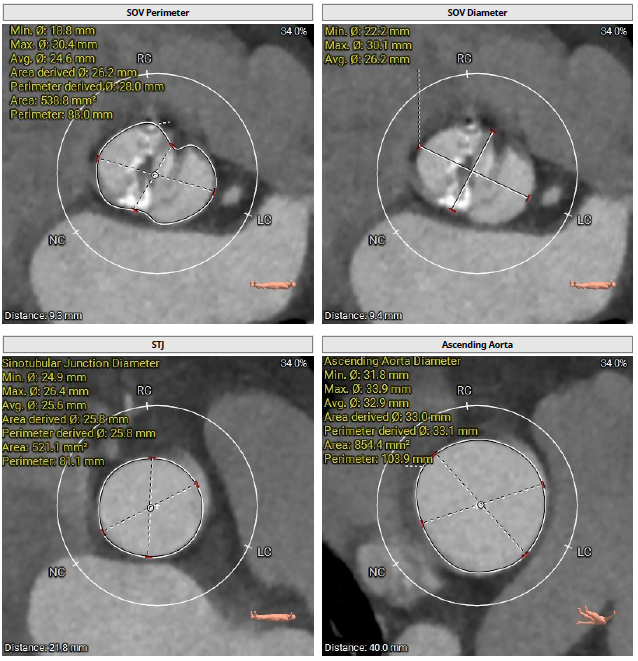

术前CT检查

该患者术前CT分析瓣环20.0mm,流出道22.0mm, Type0型二叶瓣,瓣叶轻中度钙化并增厚,瓣膜锚定力可,流出道直筒偏敞口,预估瓣膜释放后位移风险低,少量瓣周漏可能;

冠脉开口高度可,右冠瓣冗长瓣叶,预估冠脉阻挡风险低术中密切关注冠脉血流灌注,必要时冠脉保护;